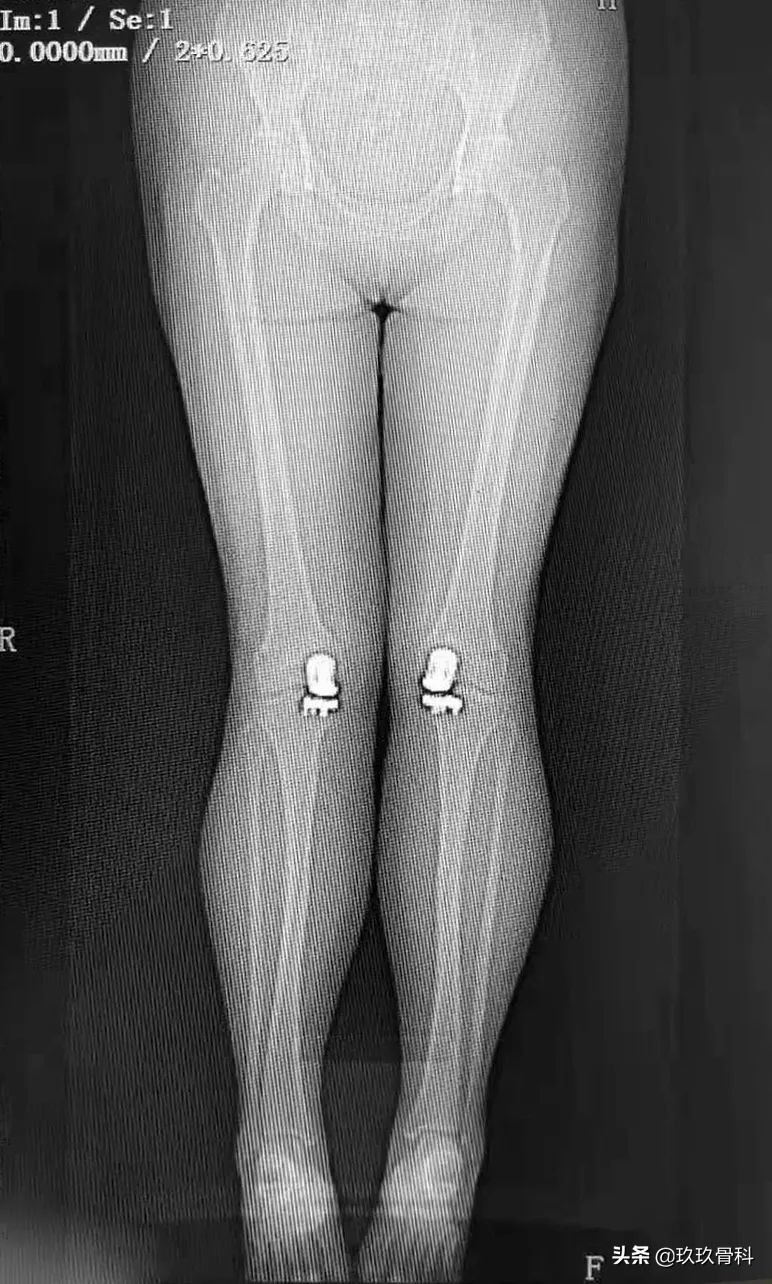

术后影像

术后第二天伸屈功能恢复良好